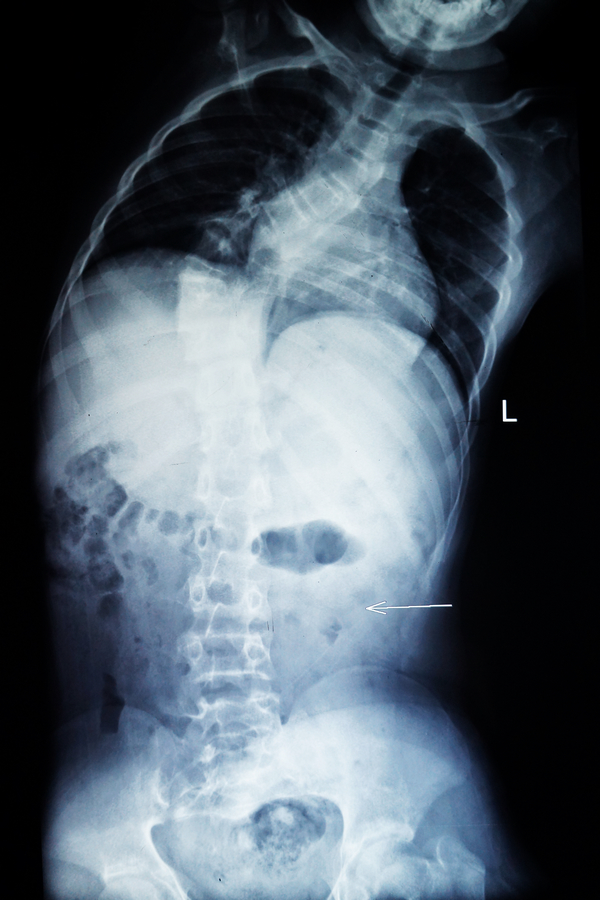

我院骨脊柱二区的医生给小松做了详细的身体检查,发现他的胸5-腰1椎体节段明显向右侧侧弯,呈小“S”形状,胸5-腰1棘突及棘突两旁无明显压痛及叩击痛,右侧竖脊肌肌张力紧张,左侧正常,站立姿势时测量左侧肩比右侧肩高约2cm。同时进行并足前屈弯腰试验时,发现小松的右侧肩胛骨明显高于左侧,出现“剃刀背”畸形,脊柱左右侧弯柔软性差,Cobb角65° ,胸腰椎MRI平扫检查确诊:脊椎侧弯畸形。

小松术前的X光片1